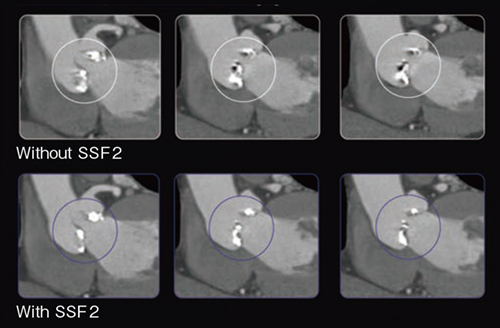

複数の臨床研究により,SSF2の効果は冠動脈画像の改善にとどまらず,心臓弁や人工弁の画像化,小児の心臓CT撮影(図3)にも有用であることが示されている。

図3 小児におけるSSF2の効果

8か月,128bpmの症例:冠動脈,左心系および右心系も動きの抑制が可能である。